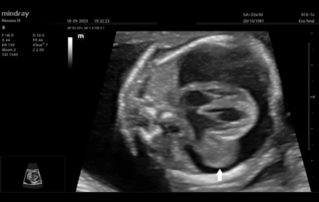

![pericardio-amniotic-shunting-fetal-intrapericardial-teratoma.thumb.319.319 Ultrasound Journal 38 - Pericardio-Amniotic Shunting for Fetal Intrapericardial Teratoma]() Ultrasound Journal 38 - Pericardio-Amniotic Shunting for Fetal Intrapericardial TeratomaLearn how ultrasound-guided fetal therapy saved a fetus with intrapericardial teratoma. Detailed case study of pericardiocentesis and shunt placement with Mindray imaging technology.Patient safety | Ultrasound Cases | Ultrasound | Women health | Cardiology | OB GYN 2025-11-19

Ultrasound Journal 38 - Pericardio-Amniotic Shunting for Fetal Intrapericardial TeratomaLearn how ultrasound-guided fetal therapy saved a fetus with intrapericardial teratoma. Detailed case study of pericardiocentesis and shunt placement with Mindray imaging technology.Patient safety | Ultrasound Cases | Ultrasound | Women health | Cardiology | OB GYN 2025-11-19 -